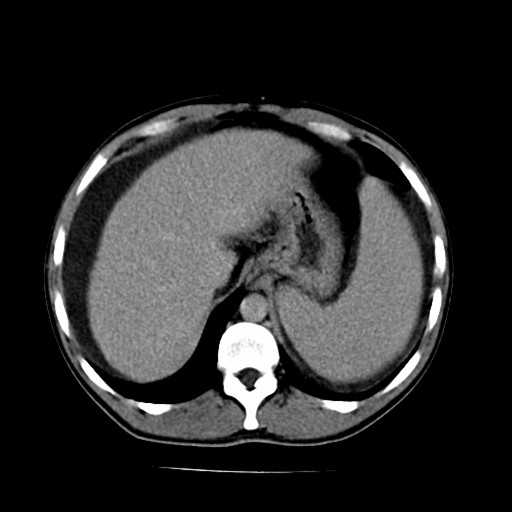

肝硬化是肝炎发展后先形成肝纤维化,然后在慢慢发展而来的,是一种比较严重的肝脏疾病,因此有很多患者会关心肝硬化是不是绝症。对此我们请肝病专家来为大家做一下详细的介绍吧!

专家指出,肝纤维化、肝硬化是一个缓慢发生的、发展的过程。如果能早期发现并积极进行干预治疗,肝纤维化是可以逆转的,早期肝硬化也是可以控制的。